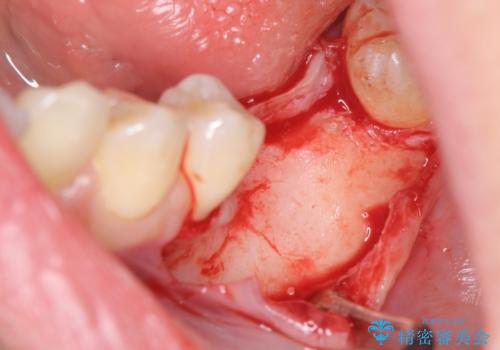

骨造成を行い安定したインプラントの環境を整える治療を計画します。

インプラントの長期的な予後を見込むには、インプラント周囲の安定した十分な骨量や清掃性、角化歯肉の存在が重要です。